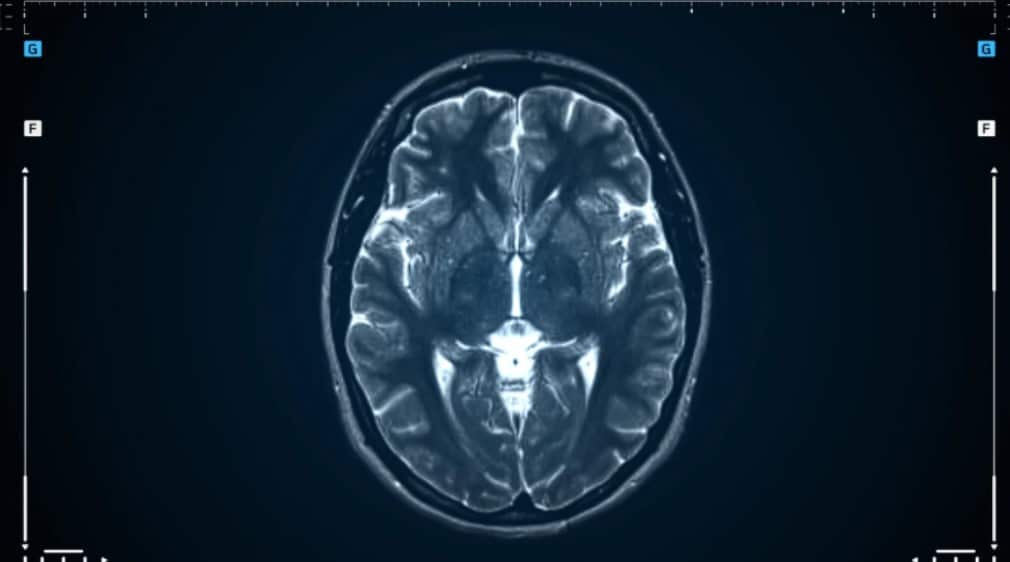

¿Por qué la resonancia magnética se ha transformado en un examen crucial en el mundo de las enfermedades neurológicas? El cerebro es uno de los órganos más complejos y fascinantes del cuerpo humano, y su correcto funcionamiento es esencial para nuestra calidad de vida. Sin embargo, cuando aparecen enfermedades neurológicas como la esclerosis múltiple, el Alzheimer o los accidentes cerebrovasculares, el diagnóstico y tratamiento oportuno pueden marcar una gran diferencia.

En el campo de la neurología, la resonancia magnética se ha convertido en una herramienta indispensable. Permite a los médicos visualizar estructuras cerebrales con un nivel de detalle sin precedentes, lo que facilita el diagnóstico temprano, la planificación de tratamientos y el seguimiento de enfermedades complejas.

La resonancia magnética es una técnica de imagenología que utiliza campos magnéticos y ondas de radio para crear imágenes detalladas del interior del cuerpo. A diferencia de otros métodos, como las radiografías o las tomografías, la RM no utiliza radiación, lo que la hace segura y no invasiva. Pero lo que realmente la destaca es su capacidad para captar imágenes de alta resolución de tejidos blandos, como el cerebro y la médula espinal.

La esclerosis múltiple es una enfermedad autoinmune que afecta el sistema nervioso central, causando inflamación y daño en la mielina, la capa protectora de las fibras nerviosas. La resonancia magnética es fundamental para:

- Detectar lesiones: Las imágenes de RM muestran áreas de inflamación y desmielinización en el cerebro y la médula espinal.

- Monitorear la progresión: Permite evaluar la efectividad de los tratamientos y detectar nuevas lesiones.

- Diferenciar la EM de otras enfermedades: Ayuda a descartar otras condiciones con síntomas similares.